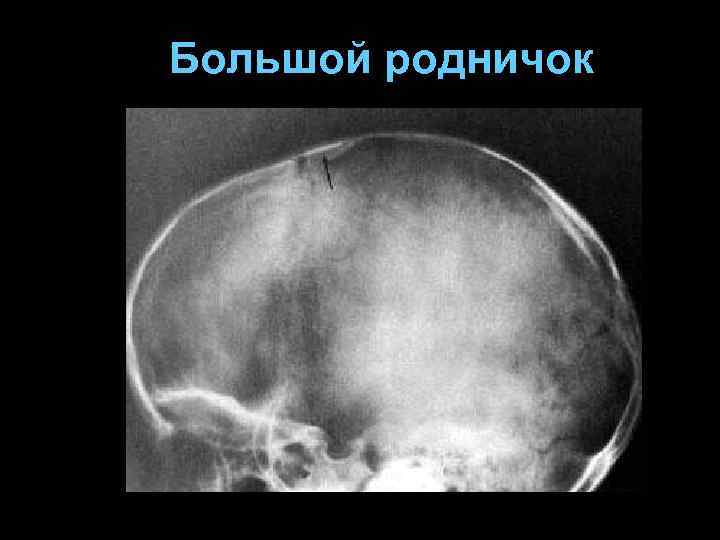

Роднички § § Передний, лобный, большой родничок (закрывается в 14 -20 мес. ) Задний, затылочный, малый родничок (2 -3 мес. ) Клиновидный родничок Сосцевидный родничок

Большой родничок